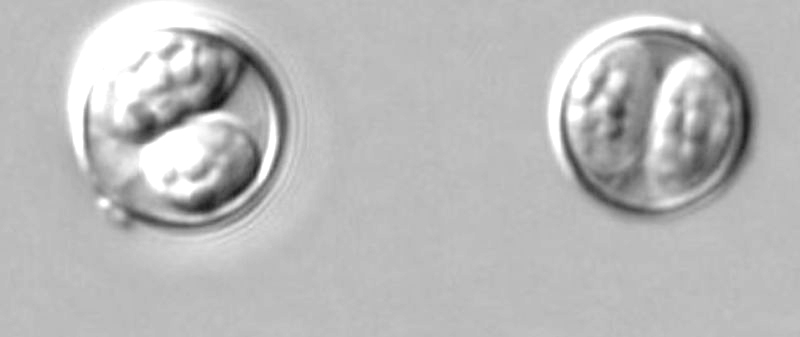

In the U.S. people can get sick with Cyclosporiasis by eating fresh produce grown outside the U.S. and contaminated with Cyclospora.CDC

Cyclosporiasis is an intestinal illness caused by a microscopic parasite, Cyclospora.

Cyclospora is spread by people ingesting something—such as food or water—that was contaminated with feces. It needs time, typically, at least 1–2 weeks, after being passed in a bowel movement to become infectious for another person. According to the Centers for Disease Control, it is unlikely Cyclospora is passed directly from one person to another, rather is transmitted through contact with tainted items.